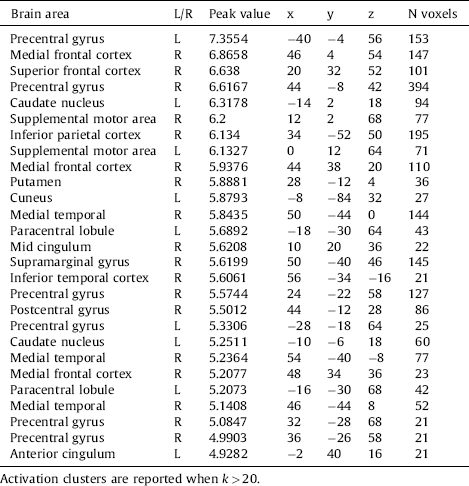

The whole brain analyses revealed no differences between the two groups on the Negative minus Neutral contrast or the Positive minus Neutral contrast. However, whole brain group differences were found in activation due to stimulus presentation in general, regardless of the valence of the stimuli. Among other regions, stronger activation was found in the supplemental motor area, frontal cortex, inferior parietal cortex and the anterior cingulum. All differences are depicted in Table 4 and Fig. 3.

Table 4 Stronger brain activity during all stimuli in the Aggression group compared to the control group.

Fig. 3 Stronger brain activation in the Aggression group during the viewing of the pictures, regardless of category. P < .05, FWE-corrected.

In this study we examined whether veterans with anger and aggression problems show different brain activation and functional connectivity in response to general, non-facial emotional stimuli. To test this, positive, negative and neutral pictures were shown during an fMRI scan. It was found that the groups showed no differences either on the negative minus neutral contrast or the positive minus neutral contrast. However, a main effect of picture presentation was found, with stronger activation in motor areas and the parietal cortex evoked by stimuli in the Aggression group compared to the Control group.

These group differences in the parietal cortex point towards increased attention to the stimuli in general, regardless of their valence in the Aggression group, possibly due to the context in which every stimulus had the potential to be negative. Indeed, attentional problems have been reported in aggression and emotion regulation before Reference Jaworska, Berrigan, Fisher, Ahmed, Gray and Bradford[38, Reference Ochsner and Gross39]. In individuals reporting dysfunctional anger, differences in levels of oscillatory EEG activity were found that were interpreted as a chronic hypervigilant state Reference Jaworska, Berrigan, Fisher, Ahmed, Gray and Bradford[38], which may lead to an overreaction to non-harmful situations. The increased cue reactivity as found in the current study might also reflect a general heightened arousal level. In line with this possibility, in an earlier study we showed that military veterans with aggression had a heightened startle response Reference Heesink, Kleber, Häfner, van Bedaf, Eekhout and Geuze[40].

Furthermore, stronger activation in motor areas points was found in the Aggression group. This could be related to impulsivity and reduced inhibition Reference Bari and Robbins[41], which are strongly associated with aggression Reference Ramirez and Andreu[42]. The concept of impulsivity refers to the tendency to act quickly, without thinking or planning. Furthermore, individuals with higher trait anger show impaired response inhibition in a Go/NoGo task Reference Pawliczek, Derntl, Kellermann, Kohn, Gur and Habel[43], and individuals with higher trait aggression showed a combination of reduced orienting but enhanced preparation for action in a threat-anticipation task Reference Gladwin, Hashemi, van Ast and Roelofs[44]. The motor-related activation in the Aggression group might therefore be related to impulsiveness and preparation to respond quickly, prior to proper stimulus discrimination, although we do not have direct measures of this.